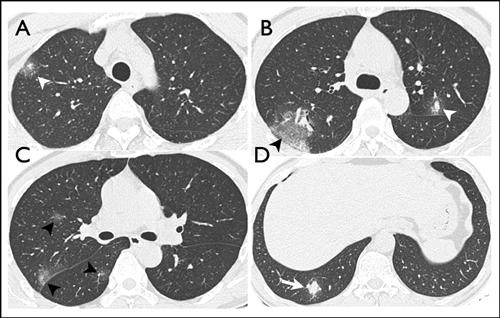

相关图片